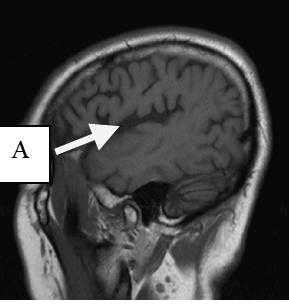

18. Image Upload 34

135. The arrow labeled “A” is pointing to is the

a. Thalmus

b. Basal Ganglia

c. Genu of the corpus collosum

d. Head of the caudate nucleus

D Head of the caudate nucleus